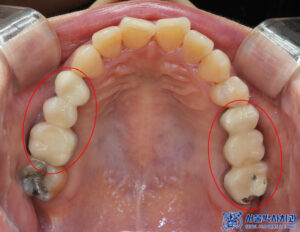

확인해 보니,

오래전 치료를 받은

브릿지 보철들이 관찰되었는데요.

보철이 마모가 되고 깨져

안에 금속이 드러나 있는

부분이 보였습니다.